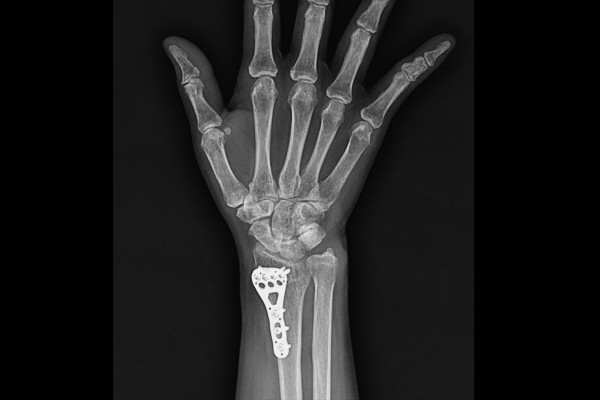

수술은 실시간 X-RAY인 C-ARM을 이용하여 정확한 위치를 확인하며 진행합니다. 먼저 골절되어 뒤로 꺾인 뼈를 제자리로 잘 맞춰준 후, 금속판(Plate)을 이용하여 강하게 고정해줍니다.